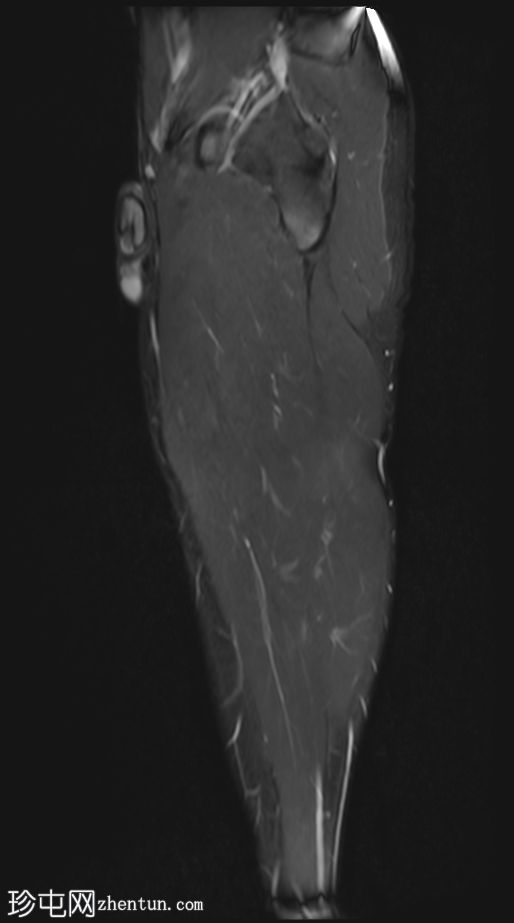

冠状位

STIR序列

股二头肌长头近端和中段可见高信号水肿,大小约10×3厘米。

此外,邻近的半腱肌可见羽毛状水肿,大小约5×2厘米。

未见肌内积液或血肿。

邻近肌间隙可见一条粗液线,延伸至近端和远端肌腱连接处。

股二头肌腱近端和中段轻度增厚,呈波浪状轮廓,腱周积液延伸至肌腱连接处。然而,未发现撕裂。